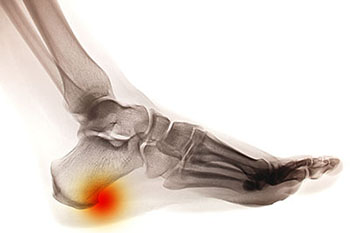

Signs that you may have a heel spur include pain felt in the heel region, swelling at the front of the heel, and inflammation. If the affected area also feels warm to the touch, you may be experiencing the symptoms of a heel spur. Heel spurs are extremely uncomfortable and can often lead to a great deal of pain if left untreated. They may develop due to excess body weight, complications with arthritis, wearing poorly fitted shoes, and bruising of the heel.

A heel spur takes the form of a bony-like growth. This is due to a calcium deposit that extends between the heel bone and foot arch. They can grow up to half an inch in length; however, they may not be outwardly visible. Because heel spurs tend to grow, increasing the overall discomfort felt, it’s important that you seek professional help as soon as pain is experienced for early detection.